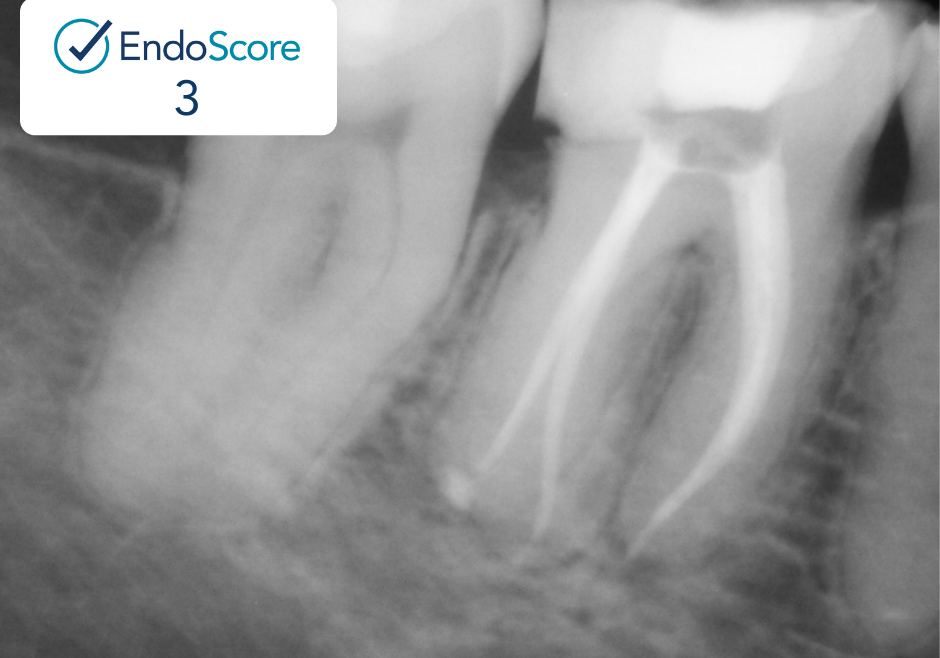

Case Study by Dr. Randy Cross

EndoScore of 3 at finish. Necrotic Symptomatic Apical Periodontitis. 2 visit with triple antibiotic paste, 30x06 conserve file with matching GP and Endoceramic sealer. Finished with bonded VistaApex clear flowable. The patient is being recalled in one year to confirm healing.

EndoScore: 3